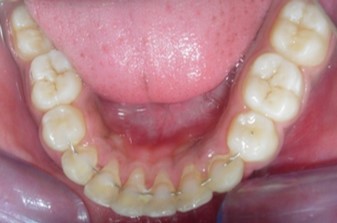

Intraoral assessment. (Figure 1d,Figure 1e,Figure 1f,Figure 1g,Figure 1h).

Figure 1h.Pre-treatment intra-oral-Lower occlusal

The maxillary arch was V-shaped with severely proclined and rotated maxillary incisors with a palatally placed 12. The mandibular arch was U-shaped with severe crowding of mandibular incisors, with 43 partially erupted and buccally placed with transpositioned 42 and 43, with 42 mesiolingually rotated, 33 distolingually rotated and 34 distolingually rotated and buccally placed.

Severe increase in overjet and deep bite were both observed. The maxillary midline coincided with the skeletal midline but the mandibular midline was shifted to the right side by 1 mm. Bilateral maxillary posterior crossbite was also observed. On right side the molar relation was Class I and on the left side it was Class II. The canine relation was Class II on the left side and the curve of Spee was increased.